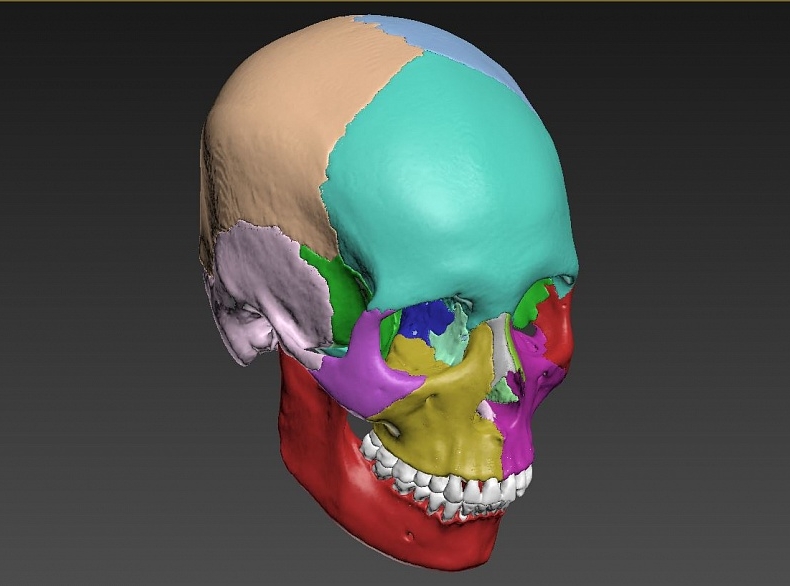

Анатомия детского черепа: Рентгеновские снимки и описание